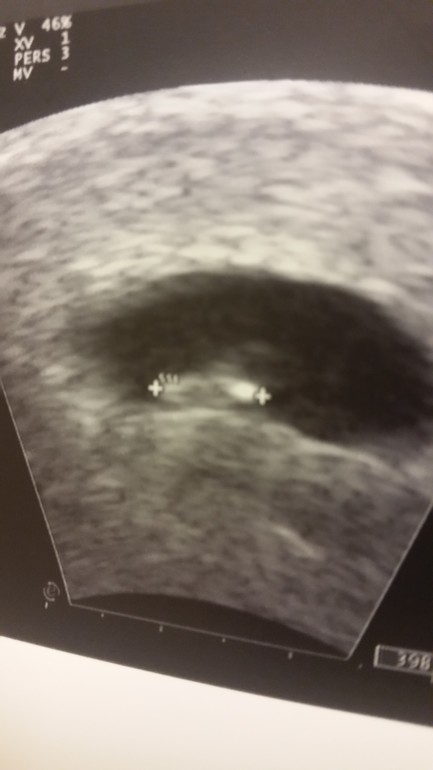

Ура! Наконец-то наш малыш показал себя во всей красе )) долго же нам пришлось ждать и высматривать 😊